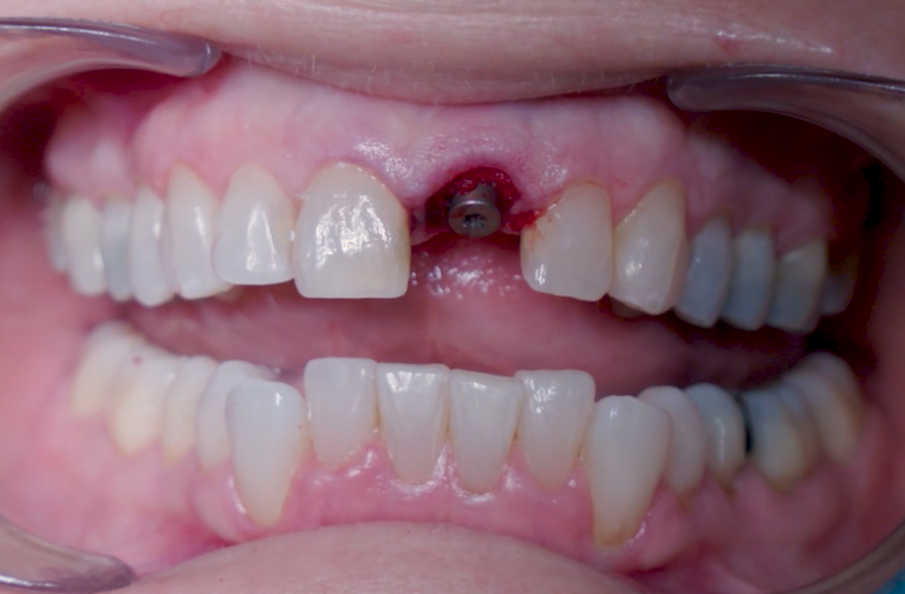

Una paziente di 53 anni si è presentata in studio con un incisivo sinistro fratturato a cui era stata più volte cementata una corona di ceramica (Figg. 1, 2). L’anamnesi e gli esami hanno evidenziato una buona salute sistemica e orale, un’occlusione ben equilibrata e nessuna abitudine al fumo. La tomografia cone beam (CBCT) e la radiografia periapicale hanno mostrato un riassorbimento radicolare esterno con inserimento nell’osso alveolare molto scarso, insufficiente per un adeguato posizionamento di un comune perno endocanalare (Figg. 3, 4). Considerando che il dente fratturato si trovava nella zona estetica, il paziente richiese un restauro nel modo più sicuro e più veloce possibile.

Fig. 1_Situazione iniziale, visione extra-orale.

Fig. 2_Situazione iniziale, visione intra-orale.